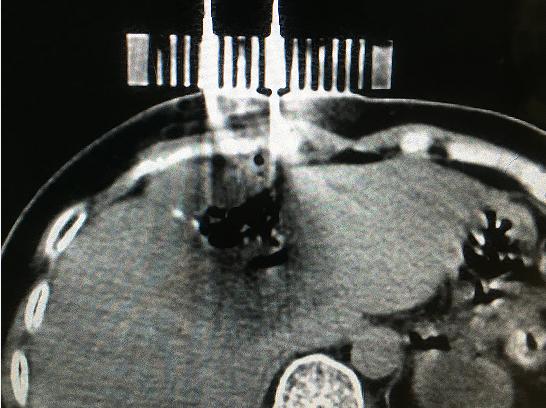

患者女性,57歲,肝癌術(shù)后5月復(fù)發(fā),病灶6.0cmx6.0cm大小,位于肝臟的右葉,靠近隔頂部,經(jīng)過多學(xué)科討論,決定實施經(jīng)皮微波消融術(shù),由于腫瘤體積較大,需要同時使用兩根消融天線進行多平面消融,為確保療效,兩根消融天線需要平行等距,但由于肝臟是不斷運動的臟器,徒手操作有一定技術(shù)難度,往往需要多次穿刺調(diào)整進針方向才能達到上述要求,為此,滕州市中心人民醫(yī)院腫瘤科張開賢主任醫(yī)師團隊借鑒既往采用模板引導(dǎo)放射性粒子植入的經(jīng)驗,創(chuàng)造性地將3D打印模板技術(shù)應(yīng)用于該例患者的消融治療,在模板引導(dǎo)下在兩個平面上平行等距插入兩根消融天線,經(jīng)過18分鐘的消融,腫瘤完全壞死,達到完全消融,患者正在術(shù)后康復(fù)之中。

3D打印模板引導(dǎo)消融的優(yōu)點:迅速將腫瘤與模板“固定”,防止因肝臟運動導(dǎo)致的穿刺不確定性;確保兩根消融天線平行等距,使熱場分布更加均勻;一次性穿刺布針成功,避免反復(fù)穿刺導(dǎo)致的腫瘤種植性轉(zhuǎn)移;模板對消融天線起到固定,防止因來回移動導(dǎo)致的消融天線位置的改變。據(jù)悉,這是國內(nèi)首例3D打印模板引導(dǎo)下的肝癌微波消融術(shù),這一技術(shù)的推廣應(yīng)用必將造福更多的腫瘤患者。(腫瘤一科 胡苗苗)